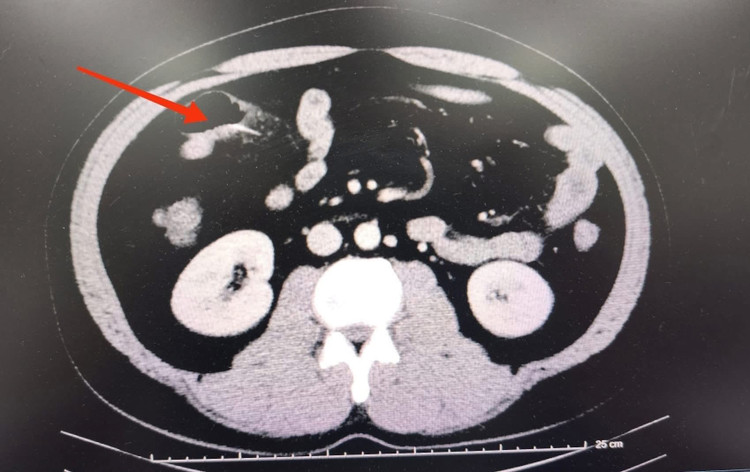

Ảnh BV